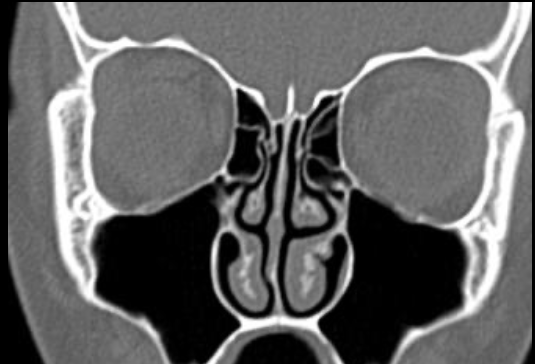

Anatomie et pathologie sinusienne